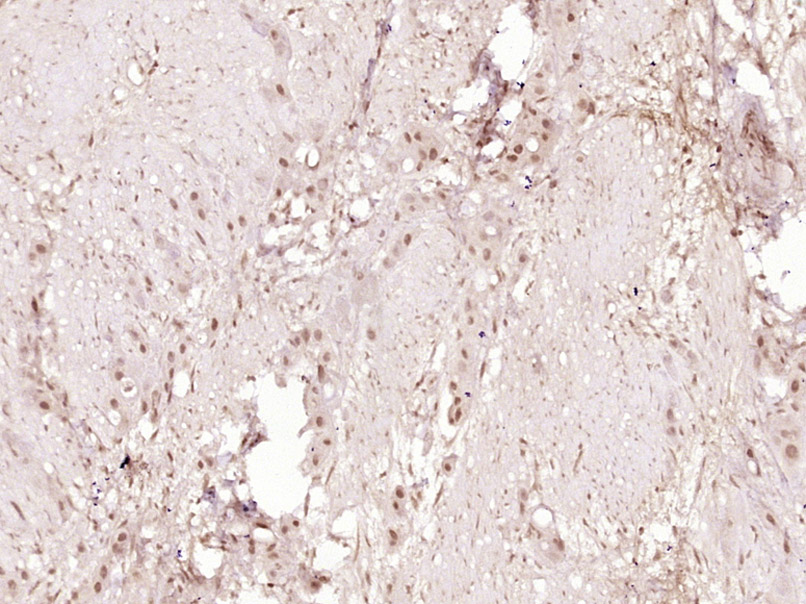

| {IHC-P} | {1:100-500} |

Primary: Anti-p-CHK2(Ser28) at 1:300

Secondary: IRDye800CW Goat anti-Rabbit at 1:10 000

Predicted band size: 61 kD

Observed band size: 61 kD